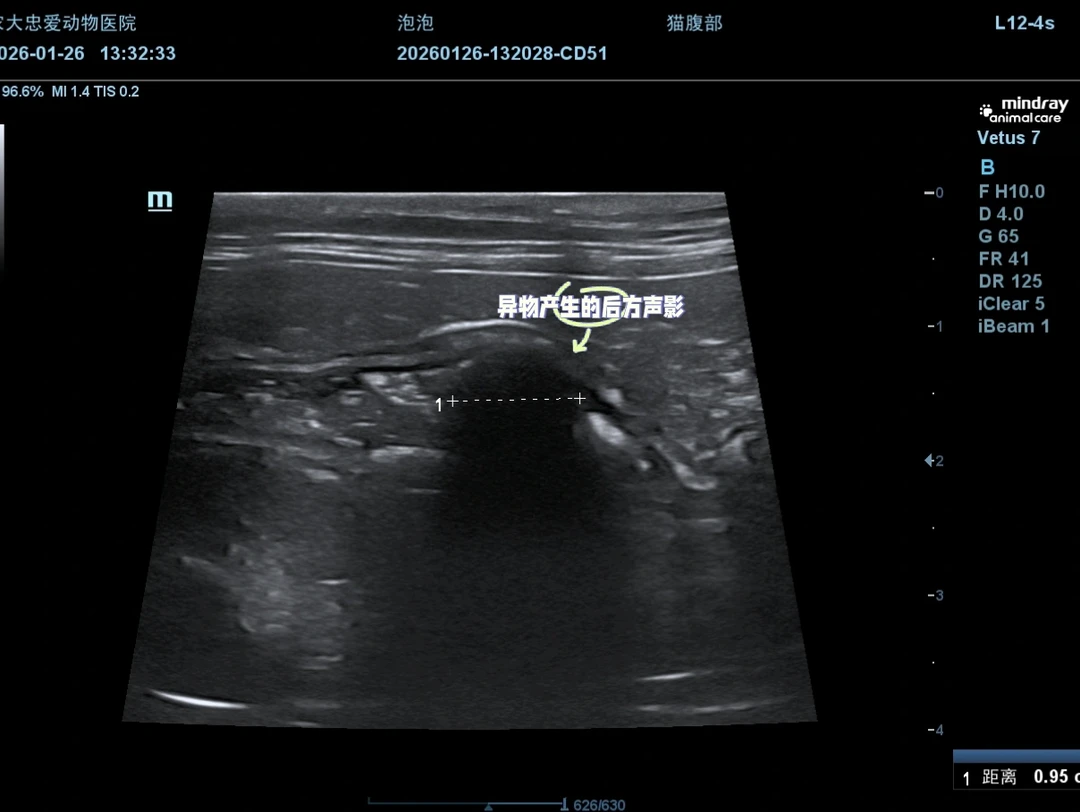

超声检查探头一放上去,十二指肠段那个异常影像就藏不住了。我心里咯噔一下:又是吞异物了。